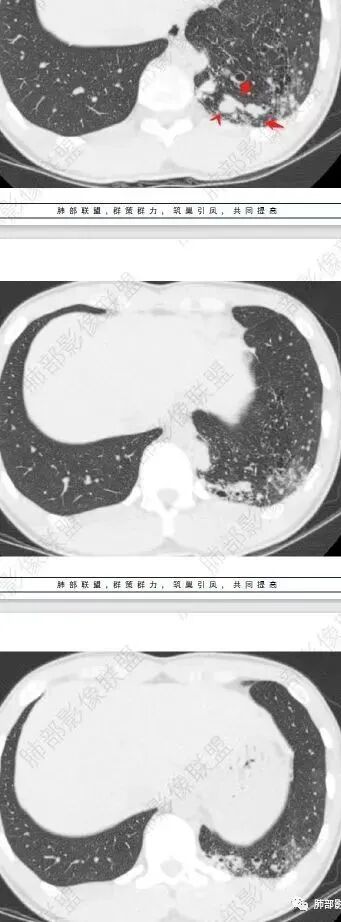

左肺下叶多发大小不等囊腔,周围伴有磨玻璃影,考虑CCAM伴感染。

左肺下叶多发大小不等囊腔伴周围磨玻璃影,可见血管增粗,似与胸主动脉相连,考虑肺隔离症,鉴别CPAM。

左肺下叶多发大小不等囊腔,囊壁略厚。周围见片状高密度影,边缘模糊不清,考虑CCAM伴感染,鉴别隔离症

左肺下叶多发囊腔、结节,及磨玻璃密度影,考虑肺隔离症,鉴别CCAM

左肺下叶多发大小不等囊腔,部分有粘液栓,周围伴有磨玻璃影,左肺下叶基底干支气管未见,双肺尖可见多发局限性透亮区,青年男性,考虑先天性气道或肺部发育畸形,支气管闭锁?CPAM?鉴别肺隔离症。

左肺下叶大小不等含气囊腔,壁厚薄不均,粘液栓,考虑 ccam,鉴别支气管闭锁,肺隔离征。

左肺下叶多发薄壁囊性病灶,血管贴边,并多发增粗的血管,还有一些斑片影,磨玻璃影;两肺尖也有薄壁囊性病灶;病史咳嗽咳痰,痰中带血,跟老师们考虑肺隔离症伴感染,鉴别LIP

左肺下叶多发囊腔,粗大血管影,隔离征可能,鉴别气道畸形。

青年男性,左肺下叶多发囊腔伴磨玻璃影,并见增粗血管影,考虑肺隔离症。

几乎无壁,低密度,胸膜下

连续的看这些管状影与肺动脉好像没有连续性,不知道是否与主动脉相连,附近高密度影,提示感染。

可见囊状影、管状影,附近血管明显增粗,似乎与肺动脉不相连